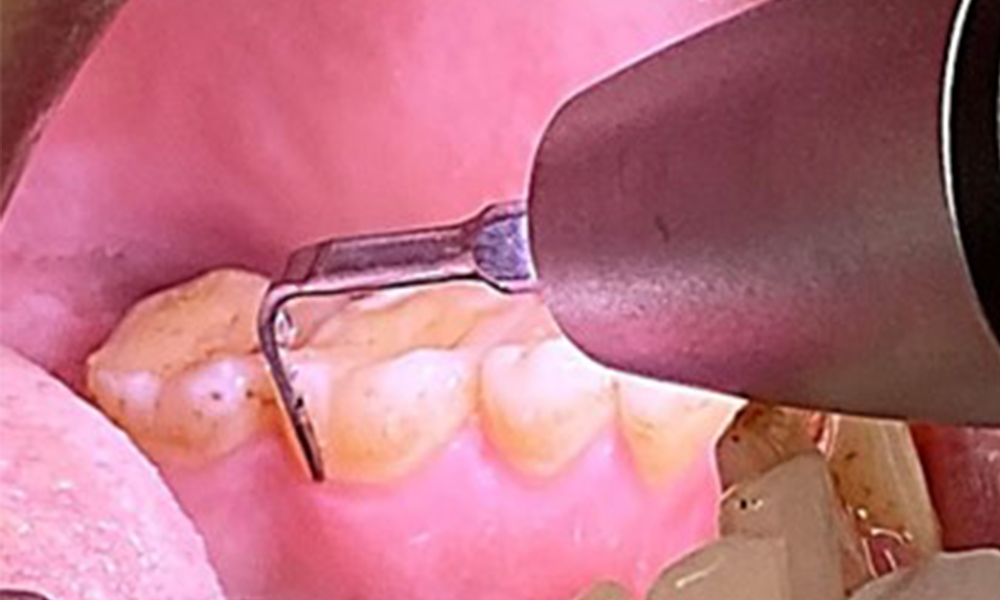

Due to the otherwise favourable general medical condition, the needs determined during the intraoral examination will be decisive for their treatment. It will be essential to periodically determine the probing depths. Gingival bleeding decreases in smokers, which is why the clinical diagnosis of periodontitis can only be made by probing (Fig. 7). Placing exclusive focus on the determination of bleeding indices may obscure existing periodontitis or gingivitis. (5)

The objective would be to control disease risk by removing supragingival and subgingival biofilm. The instruments can be selected based on patient needs. First, calculus and any concretions must be removed using ultrasonic and/or manual instruments (Fig. 10).